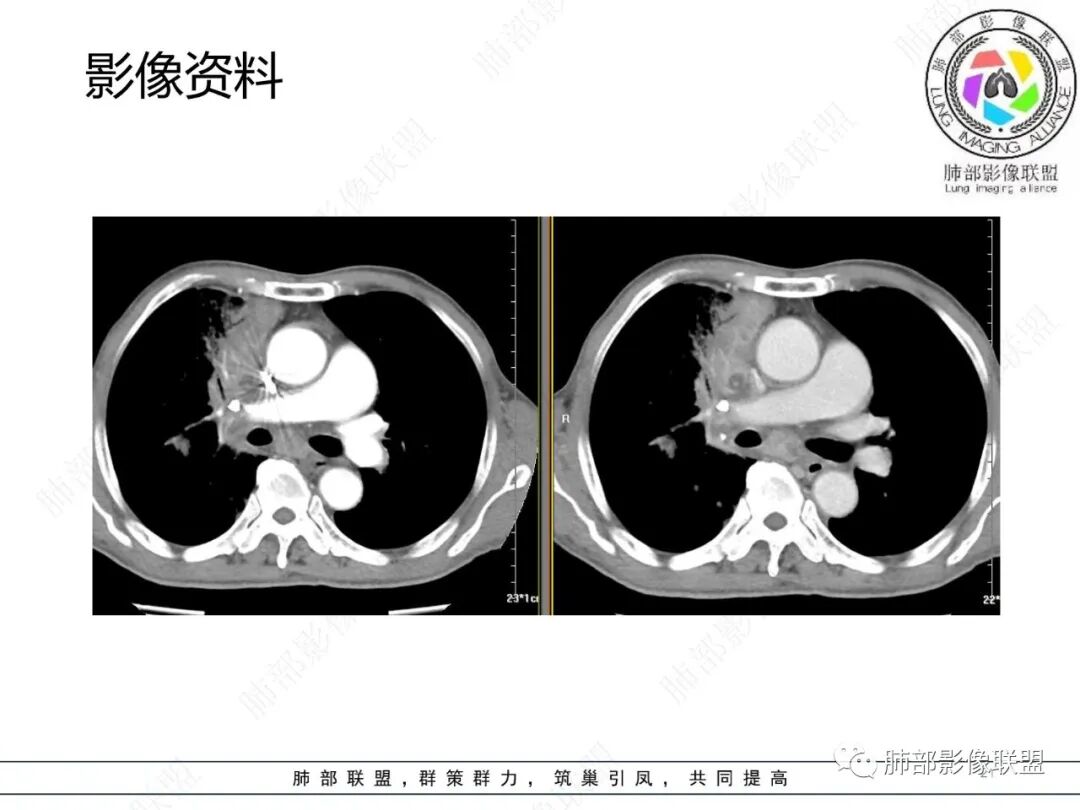

影像资料

2.胸部CT: 右肺病灶,主要累及右肺上叶前段、右肺中叶内侧段及右肺下叶背段,片状影及结节影,实性密度为主,部分磨玻璃晕,密度不均,散在钙化,其中上叶前段支气管闭塞,隐约见钙化突入。未见明确“硬树芽”或“拐枣征”。主要呈延迟强化,其间低密度区疑坏死或粘液成分。纵隔内见多组淋巴结肿大环形强化,部分钙化。

临床免疫缺陷患者呼吸系统症状易想到肺孢子菌或马尔尼菲篮状菌感染。影像不支持肺孢子菌肺炎。马尔尼菲篮状菌肺部感染影像表现多样,可以磨玻璃影、实变影,有时多发结节影酷似继发性肺结核,纵隔或远处淋巴结肿大并环形强化等须仔细甄别。有文献报道马尔尼菲篮状菌肺部感染患者82.7%胸部CT有异常改变,胸部CT表现:45.6%患者肺野斑片状浸润阴影或局限性肺实变,11.9%患者表现为结节影,11.5%患者表现为毛玻璃改变,8.4%患者表现为弥漫性粟粒样病变,5.3%患者表现为结节状肿块影。45.1%患者胸部影像学伴肺门或纵隔淋巴结肿大,23.5%患者伴胸腔积液,8.0%伴空洞病灶。